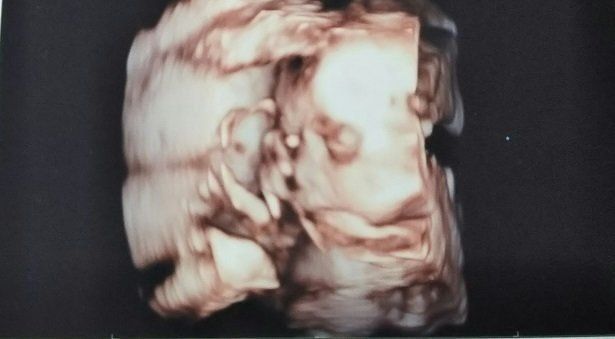

宮本真知さんの妊娠24週目のエコー写真 お顔がなかなか見られない 夏の妊娠はとにかく暑い

夏真っ盛り。妊娠前の半袖ワンピースでどうにか乗り切っていましたが、腹帯なんて暑いものは耐えられず取ってしまいました。妊娠16周目と同じく、BPD、AC、FLを測ってもらいました。赤ちゃんのおおよその体重は606g。3Dエコーでお顔をきちんと見てみようとしますが、やはり手で隠してしまうため、なかなか見られませんでした。これでも顔が写っている一番いい3Dエコー写真です。